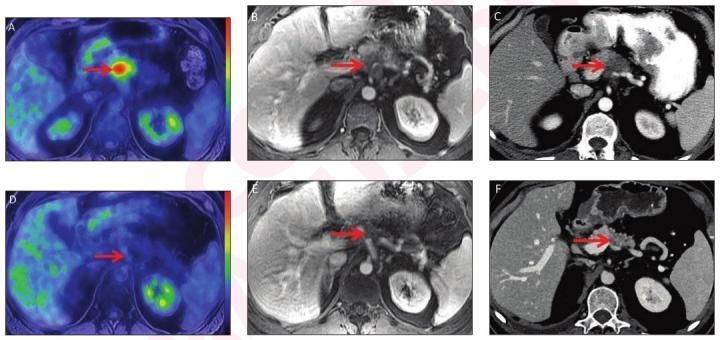

Pre-treatment (A-C) and post-treatment (D-F) images after eight cycles of systemic FOLFIRINOX and consolidative chemoradiation. Baseline CA 19-9 was 145 U/ml. Pre-treatment whole body axial fused PET/MRI showed FDG avid lesion in body of pancreas (arrow, A) with SUVmax 7.1 and SUVgluc 8.0. Lesion was hypo-enhancing on axial contrast-enhanced T1-weighted (T1W) MR image (arrow, B) from focused abdominal PET/MRI and on CT (arrow, C). Pre-treatment CT tumor volume was 10.3 cm3. Post-treatment whole body axial fused PET/MRI showed complete metabolic response (arrow D) with SUVmax 1.9 and SUVgluc 1.9. Lesion was indistinct on axial contrast-enhanced T1W MRI (arrow, E) and CT (arrow, F), and there was upstream pancreatic parenchymal atrophy. Post-treatment CT tumor volume was 0.46 cm3. There was normalization of CA 19-9. Relative change in SUVmax (ΔSUVgluc) was -73%, and relative change in SUVgluc (ΔSUVgluc) was -76%. Based on change in tumor size, response was categorized as partial response per RECIST. Relative change in tumor volume (ΔTvol) was -96%. Pathology showed major pathologic response (College of American Pathologists score 1.) Images courtesy of American Roentgen Ray Society (ARRS), American Journal of Roentgenology (AJR)

December 10, 2020 — According to an open-access Editor's Choice article in ARRS' American Journal of Roentgenology (AJR), post-neoadjuvant therapy (NAT) changes in metabolic metrics from PET/MRI and morphologic metrics from CT were associated with pathologic response and overall survival in patients with pancreatic ductal adenocarcinoma (PDA).

Panda and colleagues' retrospective study included 44 patients (22 men, 22 women; average age 62) with 18F-FDG avid borderline resectable or locally advanced PDA on pre-treatment PET/MRI, who also underwent post-NAT PET/MRI prior to surgery between August 2016 and September 2019. CA 19-9, metabolic metrics from PET/MRI, and morphologic metrics from CT (n = 34) were compared between pathologic responders (College of American Pathologists scores 0 and 1] and nonresponders (scores 2 and 3).

In borderline resectable or locally advanced pancreatic cancer undergoing neoadjuvant therapy, pre- vs. post-treatment changes in tumor metrics on PET/MRI (complete metabolic response, ΔSUVmax, ΔSUVgluc) and CT (RECIST, volume change) were associated with major pathologic response (AUC = 0.71-0.83; p < 0.05).

Reiterating that PET/MRI and CT metrics can help guide post-NAT pancreatic cancer treatment decisions, the authors of this AJR article concluded that by comparison, serum CA 19-9 was not associated with pathologic response or survival.